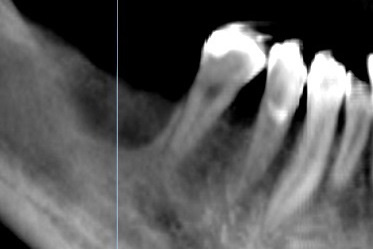

左下の奥歯2本をむし歯で失ってしまい

インプラント治療をご希望されました。 |

インプラント埋入位置や

上部構造の形態などの治療計画を3Dで作成します。 |

埋入後のレントゲン。

左上にもサイナスリフト(上顎の骨量を増やす治療)と同時に 2本のインプラントを埋入しました。 |